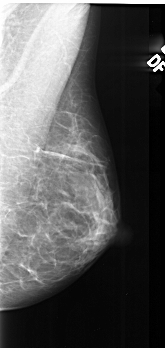

A_1022_1.RIGHT_CC

RIGHT_CC LINES 4456 PIXELS_PER_LINE 2236 BITS_PER_PIXEL 16 RESOLUTION 42 NON_OVERLAY